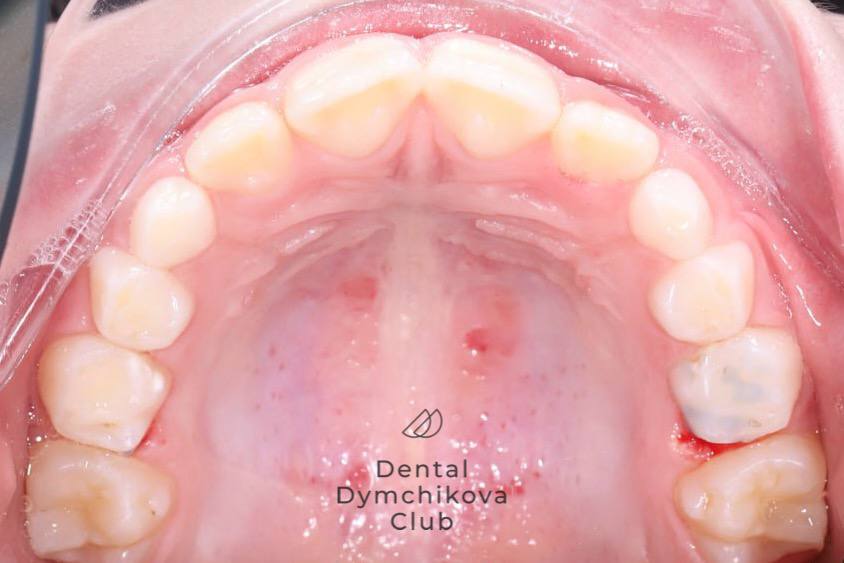

Аппарат Хаас (часть 2)

Пациент, 7 лет.

Жалобы: отсутствуют, пациент пришел на плановое снятие аппарата Хаас.

Объективно: получено место для прорезывания боковых резцов. Резцы полностью прорезались.

Лечение: снятие пластинки, рекомендовано продолжение занятий с миотерапевтом для нормализации положения языка.

Срок лечения: 8 месяцев (6 посещений у ортодонта)

Доктор: Ефимова Дарья Юрьевна